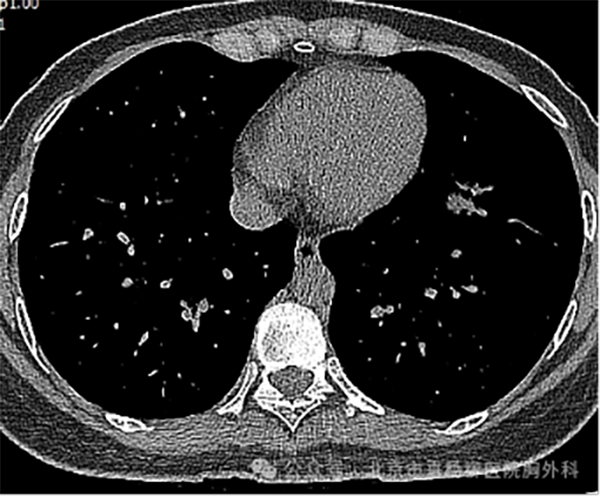

患者,女性,28岁,主因“发现左肺下叶结节3月。”来诊。查胸部增强CT:左肺下叶内前基底段部分实性病灶,长轴沿支气管走形方向,大小约4.1*1.1*2.0cm,边界清楚,周围伴磨玻璃影,边缘毛刺、分叶,其内可见空泡及支气管截断征象,周围可见血管伴行,增强扫描呈不均匀强化,恶性可能性大。考虑病人为青年患者,需慎重选择手术切除治疗及手术方式,有结节穿刺活检明确诊断指征。

术前CT

纵隔窗